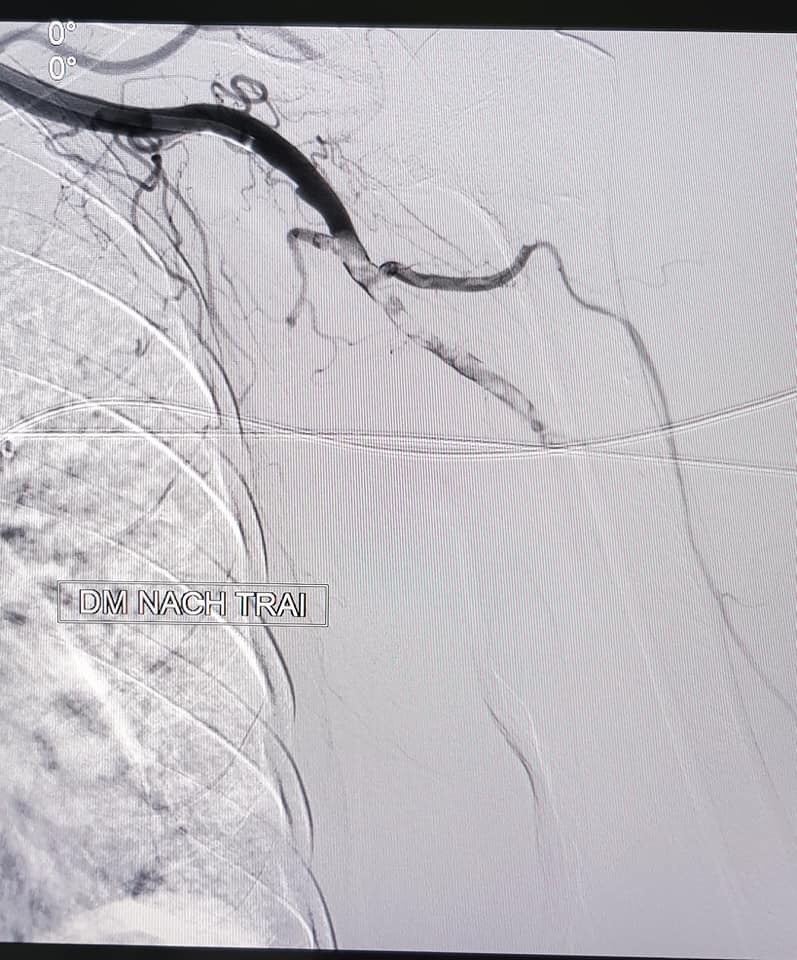

Ngày 16/11/2018, với trang thiết bị y tế hiện đại và tay nghề chuyên môn cao, các bác sĩ Bệnh viện đa khoa tỉnh Bắc Ninh đã cấp cứu thành công ca bệnh tắc động mạch chi, giúp bệnh nhân không bị cắt cụt tay trái bằng phương pháp chụp mạch số hóa xóa nền và lấy huyết khối qua ống thông điều trị tắc mạch chi. Thực hiện thành công ca bệnh này một lần khẳng định vị trí đi đầu trong triển khai các kĩ thuật khó ngay tại tuyến tỉnh của Bệnh viện đa khoa tỉnh Bắc Ninh, góp phần không nhỏ vào chăm sóc sức khỏe nhân dân trong và ngoài địa bàn.Bệnh nhân Trần Thị T (85 tuổi) ở xã Đình Tổ, huyện Thuận Thành, tỉnh Bắc Ninh có tiền sử tăng huyết áp, đái tháo đường và nhồi máu mạn tính, đã từng bị tắc mạch chi dưới nhập viện cấp cứu trong tình trạng đau, tê vùng cẳng bàn tay trái, vùng da cánh tay trái đổi màu tím đen, rối loạn cảm giác đột ngột. Ngay lập tức, Trung tâm tim mạch và khoa chẩn đoán hình ảnh đã thăm khám, hội chẩn, thống nhất chẩn đoán và điều trị bằng phương pháp can thiệp nội mạch nhằm tái thông dòng chảy cho động mạch tay trái trên hệ thống điện quang can thiệp. Dưới hướng dẫn của hệ thống số hóa xóa nền, hình ảnh tổn thương được hiển thị rõ nét, cho thấy tắc hoàn toàn động mạch nách, liên tục đến động mạch cánh tay và động mạch vùng cẳng tay.

![]() Hình ảnh chụp động mạch tay trái của bệnh nhân bị cục máu đông làm tắc hoàn toàn động mạch nách, liên tục đến động mạch cánh tay và động mạch vùng cẳng tay |